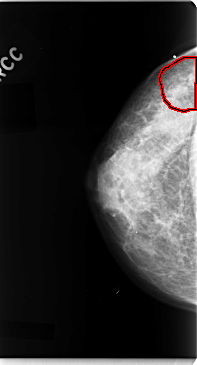

C_0077_1.RIGHT_CC

RIGHT_CC LINES 4736 PIXELS_PER_LINE 2560 BITS_PER_PIXEL 12 RESOLUTION 50 OVERLAY

FILE: C_0077_1.RIGHT_CC.OVERLAY

TOTAL_ABNORMALITIES 1

ABNORMALITY 1

LESION_TYPE MASS SHAPE IRREGULAR MARGINS ILL_DEFINED

ASSESSMENT 4

SUBTLETY 3

PATHOLOGY MALIGNANT

TOTAL_OUTLINES 1

BOUNDARY